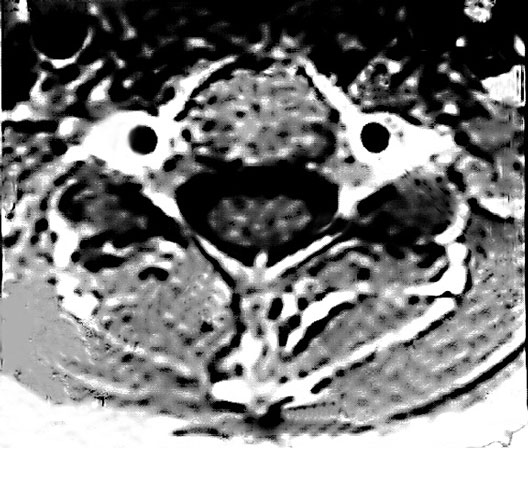

Cervical Spine Cross Zoom

1. Spinal Cord

2. Vertebral Artery in Foramen Transversarium

3. Vertebral Lamina